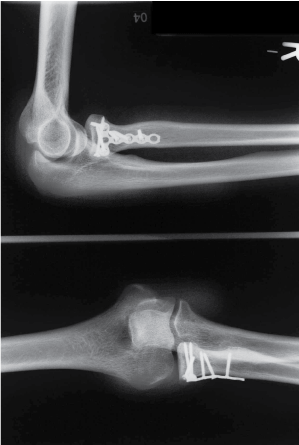

Case 1: Images 1a-d

Images of a 38 year old patient after a fall while inline skating. It was a Mason II radial head fracture with a fracture of the capitullum. Follow-up after 39 months; extension/flexion in elbow 0-5-140; pronation/supination 90-0-90. The patient had a Morrey score of 93 points and good results according to R & R.